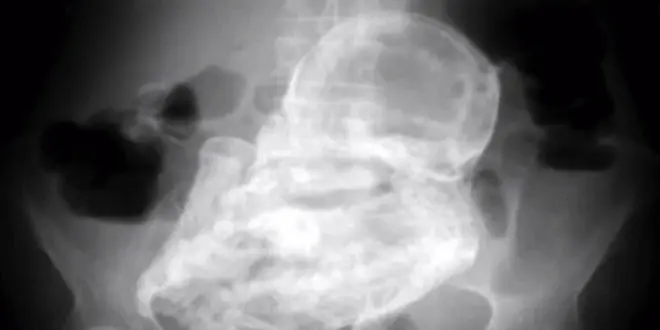

A l’issu d’un examen aux ultrasons, puis d’une radiographie de l’abdomen d’une colombienne de 82 ans, les médecins ont découvert que celle-ci était porteuse d’un lithopédion, c’est à dire un fœtus pétrifié.

Ces lithopédions se forment lorsqu’un fœtus, qui s’est développé dans la cavité abdominale – et non dans l’utérus (1) – meurt à un stade avancé de son développement.

Or, l’organisme de la femme qui le porte ne parvient pas toujours à assimiler ce corps. Dans ce cas, un processus de momification débute, accompagné de la calcification progressive, totale ou partielle (voir encadré), du fœtus et des "annexes fœtales" (placenta, sac amniotique, cordon ombilical).

La gangue de calcium qui se forme protège l’organisme de la mère de l’infection par celui du fœtus mort. C’est la raison pour laquelle la plupart des porteuses de lithopédions ignorent la survenue du phénomène, pouvant présumer avoir fait une fausse couche. Certaines ignorent même l'existence de la grossesse abdominale initiale.